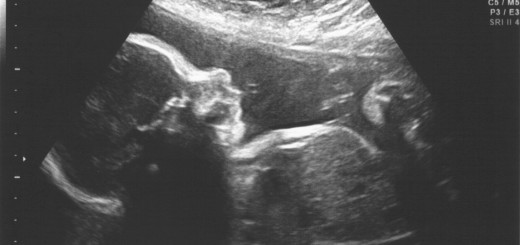

So we’re less than a week away from the due date and it already feels like a lifetime away. After my appointment yesterday with the OB, we found out that I’m 1 cm dilated! Ate some spicy jalapeno chicken for dinner last night and went out for as long a walk as I could take, but no baby activity yet.

Quick look at the calendar while at the OB, she said if baby hasn’t arrived on his own by July 3rd, we’ll plan for induction on July 9th, which seems FOREVER away. But 12 days shouldn’t take that long, right? Right?!